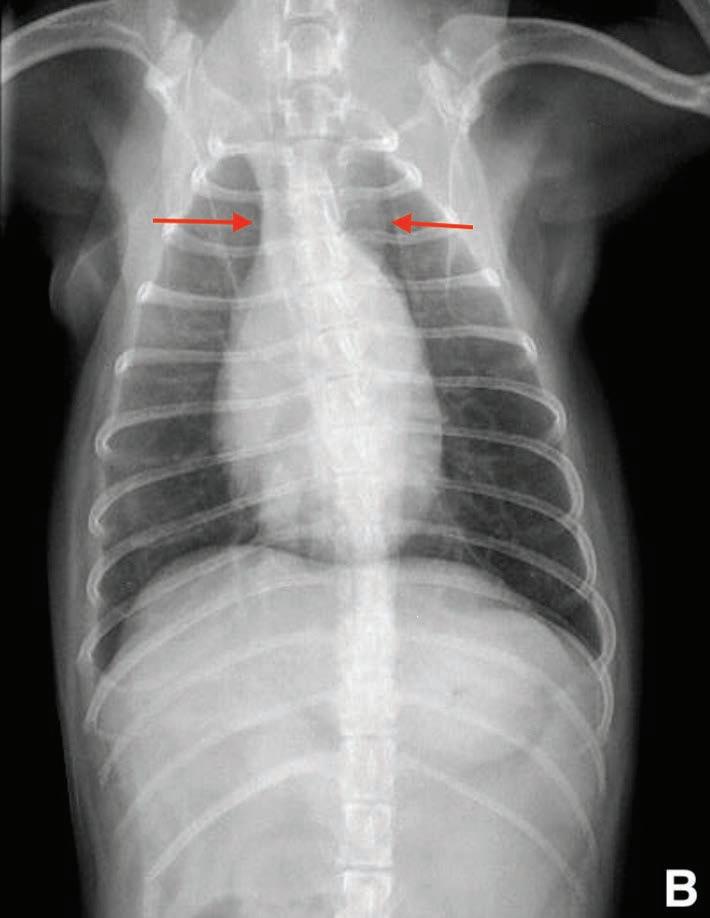

Se realizaron radiografías torácicas y en la proyección lateral derecha se observó, craneal a la silueta cardiaca, una opacidad tejido blando mal definida que producía efecto silueta positivo con esta. La tráquea se visualizó desplazada dorsalmente y el atrio izquierdo aumentado de tamaño. El parénquima pulmonar mostraba un aumento de opacidad en su área caudodorsal, compatible con un patrón pulmonar intersticial no estructurado difuso, el cual se consideró normal debido a que la radiografía fue tomada en fase espiratoria inicial

163

y a la condición corporal del paciente. En la proyección ventrodorsal, el mediastino craneal se observó en el límite superior de tamaño, presentándose un tamaño dos veces superior a la anchura de la vértebra torácica (Fig. 1). Este cambio es compatible con una imagen artefactual secundaria a la leve rotación que presenta la radiografía y a la condición corporal del paciente. El diagnóstico radiológico más probable fue una masa mediastínica craneoventral y cardiomegalia izquierda. En la ecocardiografía transtorácica se confirmó el diagnóstico de enfermedad degenerativa de la válvula

Figura 1. Radiografías torácicas en proyección lateral derecha (A) y ventrodorsal (B) donde se visualiza el área de opacidad de tejido blando craneal a la silueta cardíaca (flechas blancas). En la proyección ventrodorsal se visualiza el mediastino craneal que se presenta en el límite superior de grosor (flechas rojas).